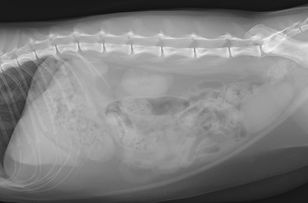

レントゲン(X線)検査

臓器の様子の検査

全身の臓器の位置や形を調べます。内部構造までわかる臓器もあります。